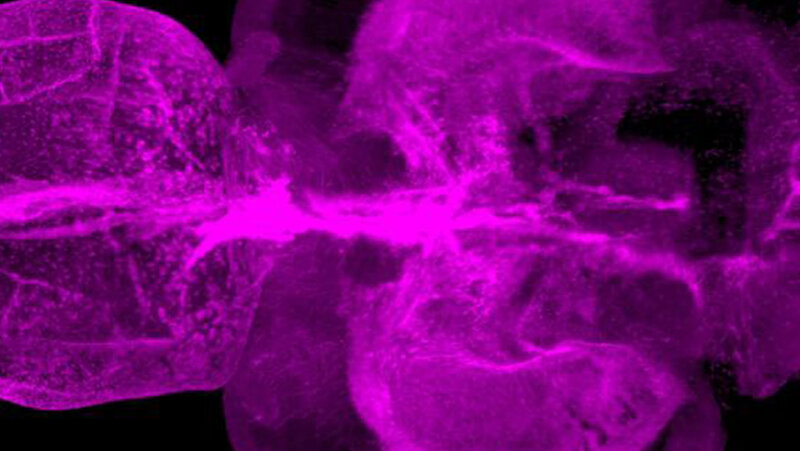

Im Gegensatz zu Säugetieren ist das Zentralnervensystem (ZNS) von Zebrafischen außergewöhnlich regenerationsfähig. Bei Verletzungen entstehen unter anderem langlebige Neuronen aus neuralen Stammzellen. Darüber hinaus führen ZNS-Verletzungen bei Zebrafischen nur zu einer vorübergehenden Reaktivität von Gliazellen, was die Integration von Nervenzellen in verletzten Regionen des Gewebes erleichtert. „Die Idee war, Unterschiede zwischen Zebrafischen und Säugetieren herauszuarbeiten, um zu verstehen, welche Signalwege im menschlichen Gehirn die Regeneration hemmen – und wie wir hier vielleicht eingreifen können“, sagt Ninkovic. Die Wissenschaftlerinnen und Wissenschaftler erzeugten gezielt ZNS-Läsionen in Zebrafischen, worauf Mikroglia aktiviert wurden. Gleichzeitig fanden die Forschenden in den Läsionen eine Ansammlung von Lipidtropfen und von TDP-43-haltigen Strukturen. Bislang wurde das Protein TDP-43 vor allem mit neurodegenerativen Erkrankungen in Verbindung gebracht.

Im Zebrafisch-Modell spielte weiterhin Granulin eine wichtige Rolle. Dieses Protein trug dazu bei, die Lipidtröpfchen und TDP-43-haltigen Strukturen zu beseitigen, worauf die Mikroglia von der aktivierten Form in die Ruheform übergingen. Es kam zur narbenlosen Regeneration der Verletzung. Zebrafische mit experimentell erzeugtem Granulinmangel hingegen zeigten eine ähnlich schlechte Regeneration der Verletzung wie Säugetiere. „Wir gehen deshalb davon aus, dass Granulin eine wichtige Rolle bei der Regeneration von Nerven im Zebrafisch spielt“, sagt Ninkovic.

Um den Vergleich zwischen Menschen und Zebrafischen weiterzuführen, hat Ninkovics Team Material von Patientinnen und Patienten, die aufgrund von Gehirnverletzungen verstorben waren, untersucht. Auch hier korrelierte das Ausmaß der Mikroglia-Aktivierung mit der Ansammlung von Lipidtröpfchen und TDP-43-haltigen Strukturen. Die entsprechenden Signalwege im humanen Gewebe waren also mit Zebrafischen vergleichbar.